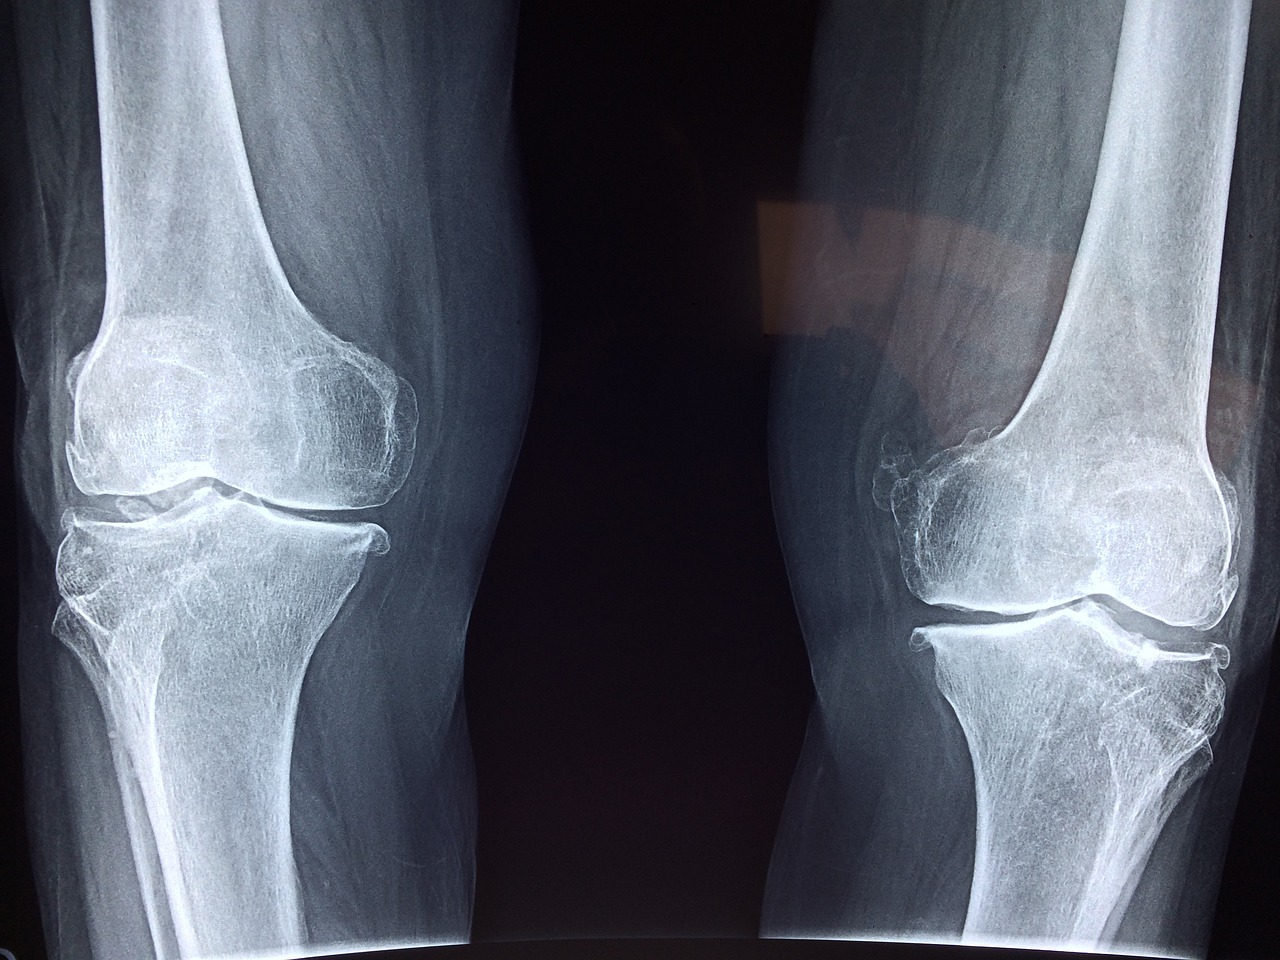

무릎연골연화증이란?

무릎 앞쪽, 즉 슬개골(무릎뼈) 아래에 있는 연골이 약해지고, 말랑해지면서 통증이 생기는 질환입니다. 계단 오르내리기, 쪼그려 앉기, 오래 앉았다가 일어날 때 무릎 앞쪽이 욱신거린다면 의심해볼 수 있습니다.